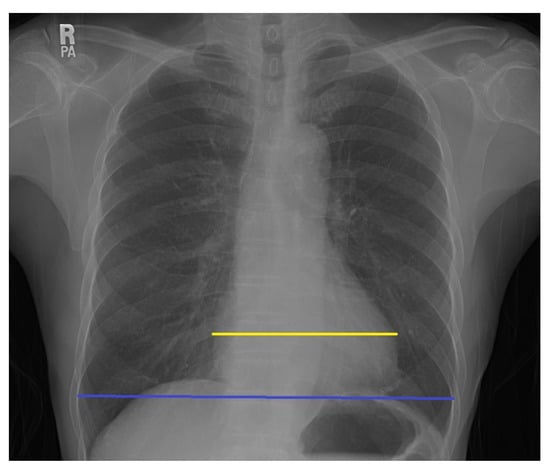

2.2. Measurement

- Mensah, Y.B.; Mensah, K.; Asiamah, S.; Gbadamosi, H.; Idun, E.A.; Brakohiapa, W.; Oddoye, A. Establishing the Cardiothoracic Ratio Using Chest Radiographs in an Indigenous Ghanaian Population: A Simple Tool for Cardiomegaly Screening. Ghana Med. J. 2015, 49, 159–164. [Google Scholar] [CrossRef] [PubMed]

- Hada, Y. Cardiothoracic ratio. J. Cardiol. 1995, 26, 51–54. [Google Scholar]